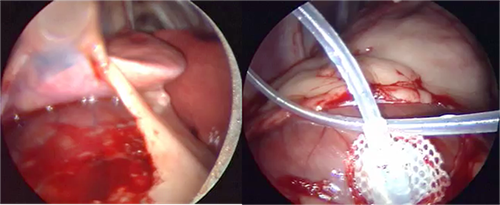

Photos 1&2: Thoracoscopic pericardectomy performed without pulmonary exclusion in 9 dogs.

Dupré G, Corlouer J, Bouvy B (2001). Vet Surg 30(1)21-7